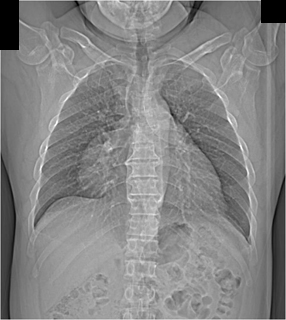

The best diagnosis in this case is

Ebsteins Anomaly

Congenital absence of the pericardium